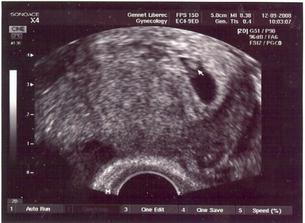

1.9.2008 těhotenství potvrzeno ultrazvukem .............................................

9.9.2008 kontrolní ultrazvuk - čekáme DVOJČÁTKA .............................................